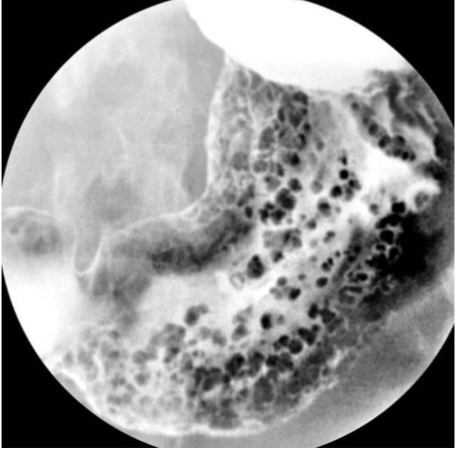

What is this and what type of scan

gastric polyps, barium swallow